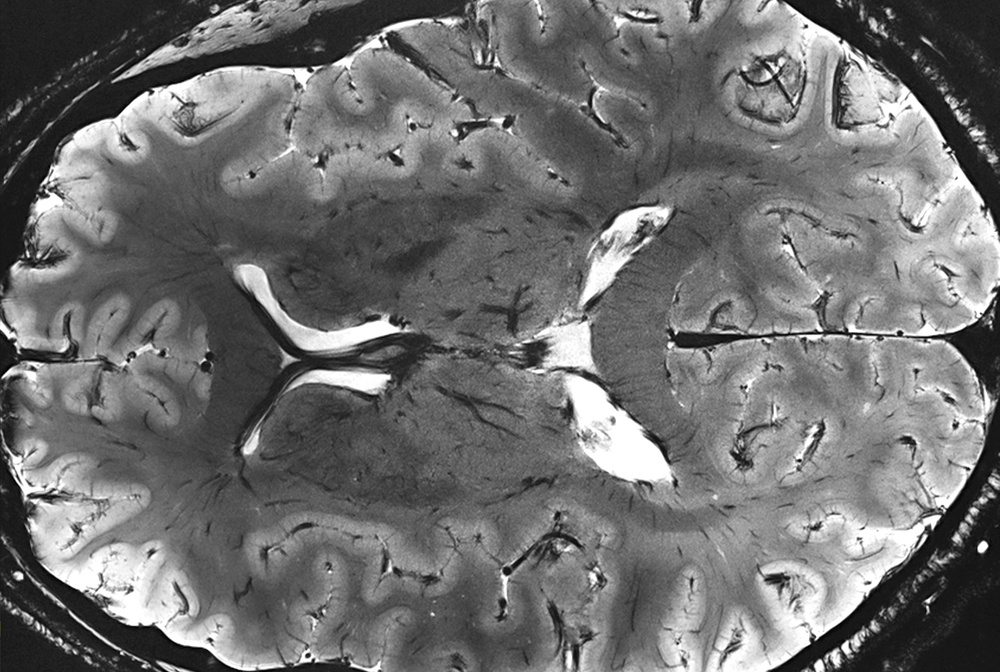

A brain scan from a 7T MRI scanner at the Athinoula A. Martinos Center for Biomedical Imaging at Massachusetts General Hospital shows microscopic detail that would be unobservable with conventional scanners. Defense Logistics Agency Energy Aerospace Energy provided Harvard Medical School with the liquid helium needed to power the scanner. Photo courtesy of Athinoula A. Martinos Center.